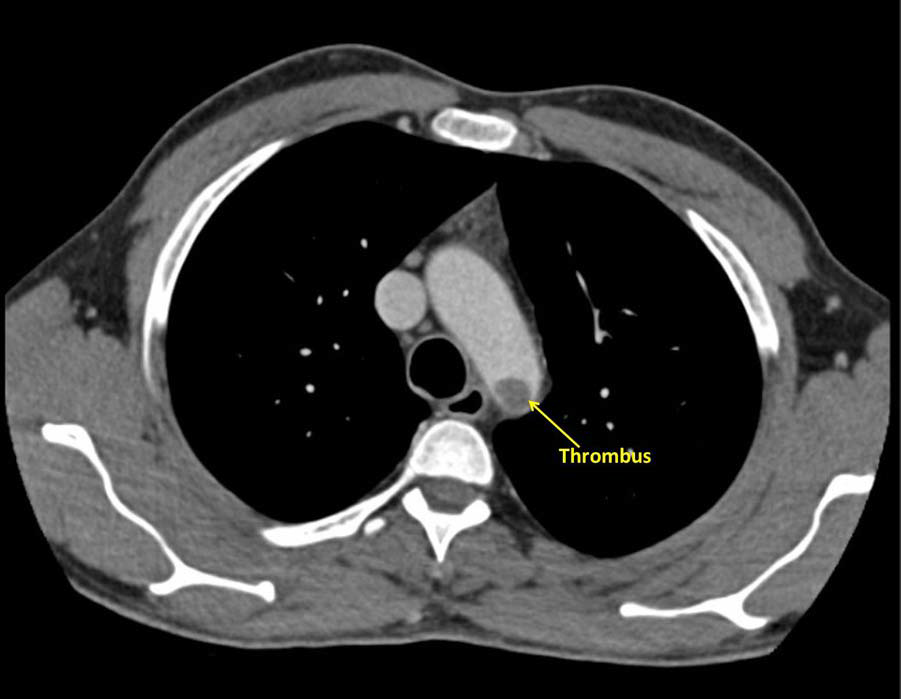

CT aortogram revealed a large, immobile thrombus fixed in the arch of aorta causing subtotal occlusion of the ostium of the left subclavian artery, with the rest of the aorta having no evidence of atherosclerosis or aortitis and the coronaries were normal (figures 1–3).

Figure 2 Sagittal view of a large thrombus attached to the descending aorta at the origin of the subclavian artery.